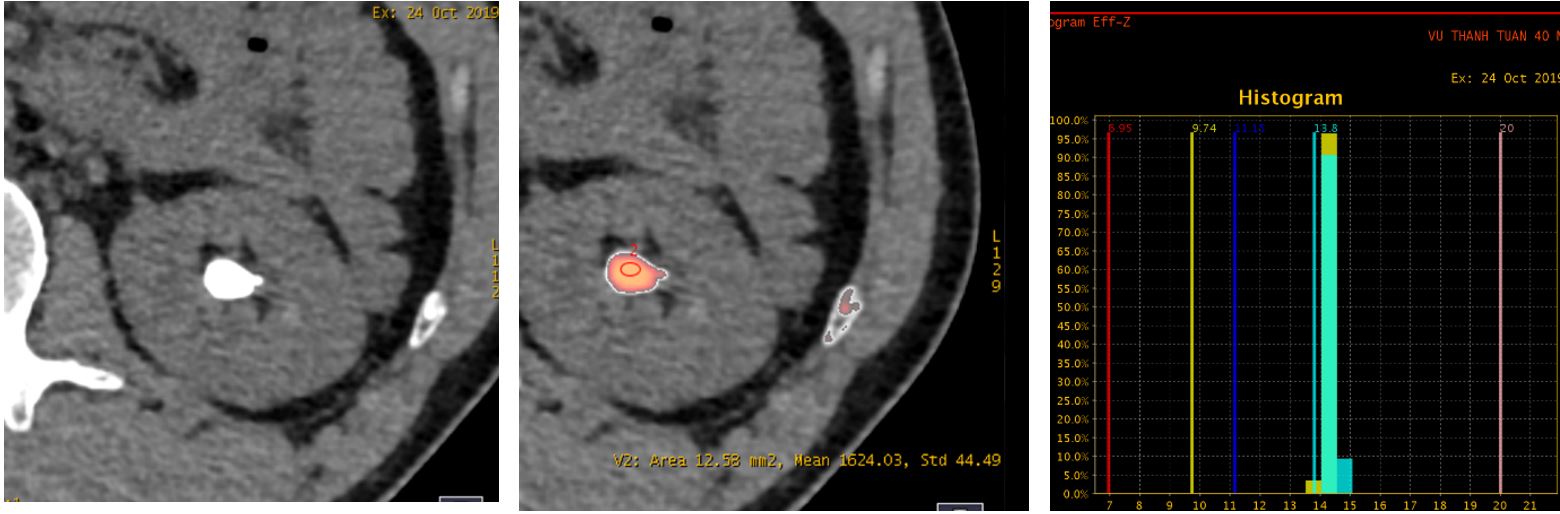

6. Đánh giá chảy máu não sau can thiệp tái thông động mạch não trên các bệnh nhân đột quị não cấp tính: Xác định chính xác bệnh nhân có chảy máu não hay chỉ là tăng tính thấm thành mạch, tiên lượng nguy cơ chảy máu của bệnh nhân sau can thiệp tái thông.

Hình ảnh sau can thiệp tái thông cho thấy tăng tính thấm thành mạch (iốt trong thuốc cản quang), không phải chảy máu não